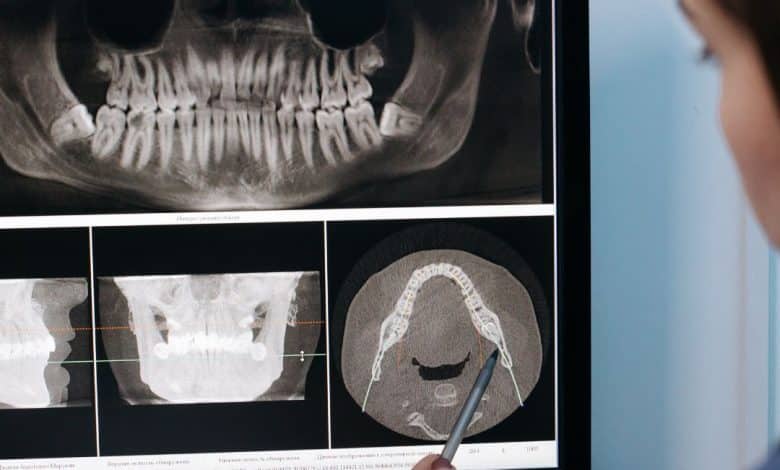

L’utilizzo di strumenti digitali è diventato uno dei principali indicatori di qualità nell’implantologia. Scanner intraorali, software di pianificazione tridimensionale e CBCT permettono di analizzare l’anatomia del paziente in modo preciso e di progettare l’intervento prima di eseguirlo. Un professionista aggiornato integra queste tecnologie nel proprio percorso clinico per ridurre margini di errore e migliorare il controllo operativo.

Gli odontoiatri certificati AIDA vengono formati per utilizzare questi strumenti in modo approfondito e responsabile, trasformando la tecnologia in un fattore di sicurezza reale. La pianificazione 3D è oggi una componente chiave del trattamento, non un accessorio. Uno studio che investe in diagnostica avanzata dimostra attenzione alla qualità e alla predicibilità del risultato.